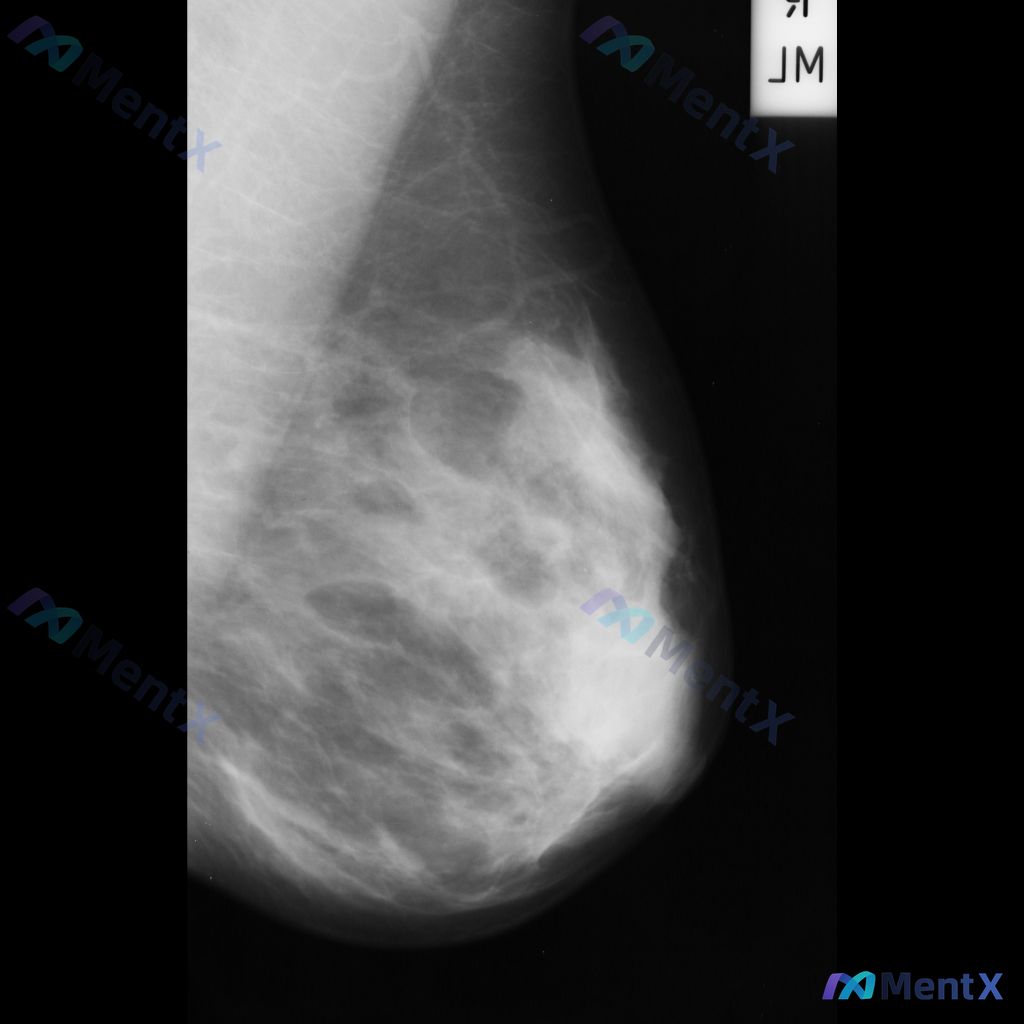

整理到一张乳腺钼靶片的读片资料,想和大家讨论下判断方向。 基本情况: - 影像:右侧乳腺内外斜位(MLO)钼靶 - 背景:致密型乳腺(多量腺体型/不均匀致密) 异常表现: 1. 右乳中上象限可见一局限性不对称致密影,形态不规则,边界部分模糊,与周围腺体融合 2. 该区域周围可见可疑结构扭曲,小梁结构...